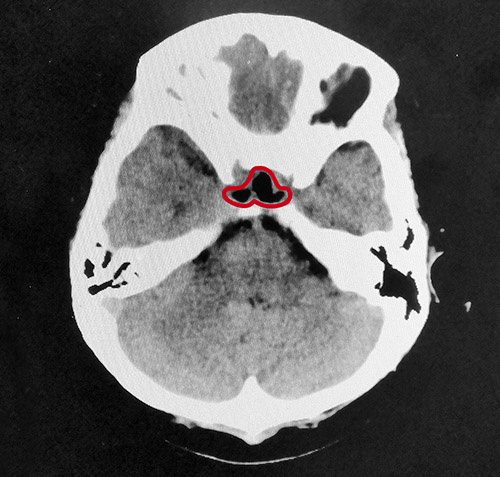

▲术后影像:肿瘤切除干净,鞍内脑脊液填充